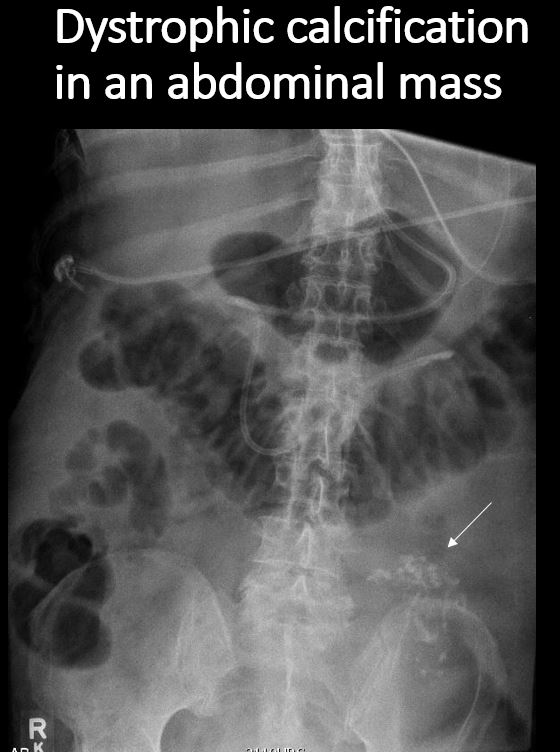

There are dystrophic or additional intra-abdominal soft tissue calcifications. |

No | NA |